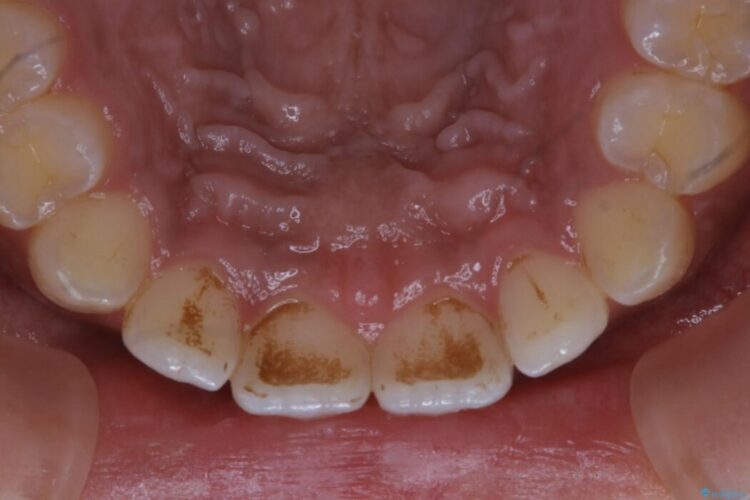

タバコによって付着したステインを綺麗にしたいとのことで来院されました。

ステインがこびりついていたため、PMTC60分コースを行いました。